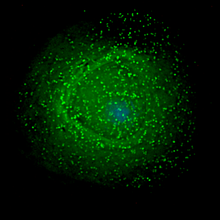

Human immunodeficiency virus (HIV) is a lentivirus (slowly replicating retrovirus) that causes acquired immunodeficiency syndrome (AIDS), a condition in humans in which progressive failure of the immune system allows life-threatening opportunistic infections and cancers to thrive. Infection with HIV occurs by the transfer of blood, semen, vaginal fluid, pre-ejaculate, or breast milk. Within these bodily fluids, HIV is present as both free virus particles and virus within infected immune cells.

HIV infects vital cells in the human immune system such as helper T cells (specifically CD4+ T cells), macrophages, and dendritic cells. HIV infection leads to low levels of CD4+ T cells through a number of mechanisms including: apoptosis of uninfected bystander cells, direct viral killing of infected cells, and killing of infected CD4+ T cells by CD8 cytotoxic lymphocytes that recognize infected cells. When CD4+ T cell numbers decline below a critical level, cell-mediated immunity is lost, and the body becomes progressively more susceptible to opportunistic infections.

The term viral tropism refers to which cell types HIV infects. HIV can infect a variety of immune cells such as CD4+ T cells, macrophages, and microglial cells. HIV-1 entry to macrophages and CD4+ T cells is mediated through interaction of the virion envelope glycoproteins (gp120) with the CD4 molecule on the target cells and also with chemokine coreceptors.

Macrophage (M-tropic) strains of HIV-1, or non- syncitia-inducing strains (NSI) use the β-chemokine receptor CCR5 for entry and are, thus, able to replicate in macrophages and CD4+ T cells. This CCR5 coreceptor is used by almost all primary HIV-1 isolates regardless of viral genetic subtype. Indeed, macrophages play a key role in several critical aspects of HIV infection. They appear to be the first cells infected by HIV and perhaps the source of HIV production when CD4+ cells become depleted in the patient. Macrophages and microglial cells are the cells infected by HIV in the central nervous system. In tonsils and adenoids of HIV-infected patients, macrophages fuse into multinucleated giant cells that produce huge amounts of virus.